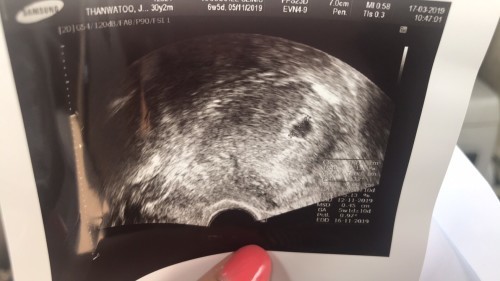

ไปตรวจมา หมอบอกว่าอายุครรภ์ 5 วีค แต่ถ้านับจากประจำเดือนไม่มาคือ 6 วีค เห็นถุงน้ำ แต่ไม่เห็นตัวเด็ก อาจจะท้องลม ทำให้เราไม่สบายวิตกกังวลมาก แบบนี้คือต้องเปลี่ยนที่ตรวจใหม่ หรือรอไปก่อนคะ กังวลมาก

อายุครรภ์เท่ากันเลยค่ะ 6 w. แต่เครื่อง u/s วัดได้ 5 w ต่างกันประมาณ 6 วัน เจอแต่ถุงเหมือนกันค่ะ หมอนัดอีก 2 w ไม่ต้องกังวลนะคะ น้องยังเล็กมาก เดี๋ยวรอบหน้าก็เจอค่ะ ถ้าไม่มีเลือดออกไม่ต้องกังวลค่ะ

วันนี้ตรวจ 5w ค่ะ เจอแต่ถุงการตั้งครรภ์ ไม่เจอตัวอ่อน หมอเจาะเลือดดูฮอร์โมนการตั้งครรภ์ ฮอร์โมนขึ้นแต่น้อยมาก หมอนัดอีกทีอาทิตย์หน้า ซาวน์ดูอีกรอบ เป็นกำลังใจให้นะคะ สู้ๆ ค่ะ ✌🏼❤️

5wยังเล็กเกินไปค่ะ 6wของเราน้องยังแค่0.20เองค่ะ รอสัก8wนะคะคุณแม่ จะเห็นชัดเจนขึ้นมากค่ะ ซาว์ดผ่านช่องคลอดถึงเห็นชัดค่ะ ถ้าซาว์ดทางหน้าท้อง ของเราคุณหมอมองไม่ค่อยเห็นเลยค่ะ

ของบ้านนี้เพิ่งซาวด์มาเมื่อวันที่7ค่ะ 5w4d เห็นแต่ถุงการตั้งครรภ์ยังไม่เห็นน้อง หมอบอกค่อยซาวด์ใหม่ตอนเดือนหน้า บ้านนี้ก็แอบกลัวเหมือนกันค่ะ เคยแท้งเมื่อปีที่แล้ว